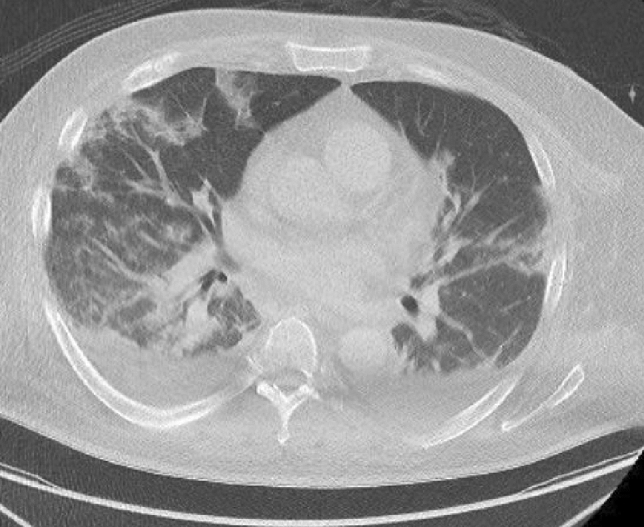

Fig. 1.

CT of the chest showing pleural effusions, bilateral patchy consolidations and ground-glass opacities